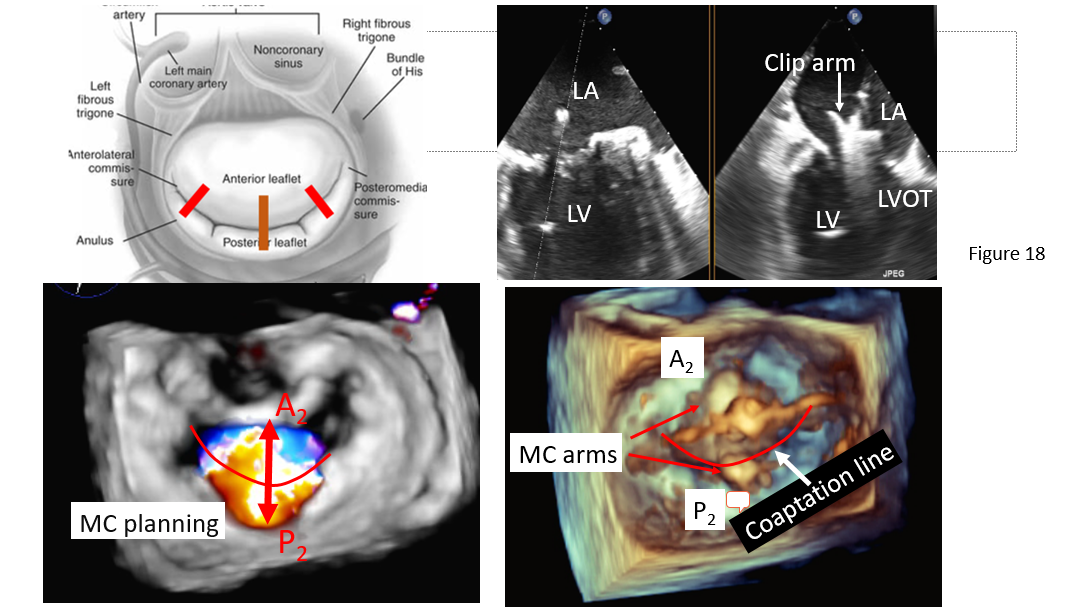

Medial-lateral clip adjustments and clip arm alignment are monitored in 3D enface view (Figure 17) upper left and lower left and right) and anterior-posterior adjustments in an orthogonal mid-esophageal biplane 2-chamber or commissure view and long-axis (LVOT) view (Figure 17). If the device is too far or close to the mitral valve, the device system would need to gain or reduced device height which can be manipulated by implanter to gain or shed height (Figure 3, I and J) accordingly. Similarly, if device is too medial or too lateral to the target lesion, implanter would need to adjust the device to the desire location and perpendicular (Figure 3 K) to the coaptation line at the lesion between anterior and posterior leaflet (Figure 3, C and D). To achieve good clip alignment, both arms of the opened clip can be visualized in full length in the long-axis view/LVOT view (Figure 17 right upper). The tip of the clip should be directed towards the largest proximal isovelocity surface area (PISA) or the location of mitral lesion. A single 3D enface view of mitral valve allows to determine if the clip is adequately positioned above the middle segments of the mitral valve and whether orientation is perpendicular to the line of mitral valve coaptation. Alignment of both arms perpendicular to mitral leaflet coaptation line is also checked with LVOT view with symmetrical and equal length of both arms. Location of the clip device is checked with commissural view for medial-lateral location and LVOT view for anteroposterior positioning.

Figure 18: Clip arm orientation perpendicular to the coaptation line of each mitral leaflet component. Left upper: A schematic illustration of anterior and posterior leaflet coaptation line with assumed mitral clip perpendicular to A2/P2 coaptation in most common cases (solid line), in unusual case of mitral clip to A1/P2 or A3/P3 (dash line). Right upper: Biplane TEE commissure/LVOT view to demonstrate arm alignment perpendicular to mitral coaptation at A2/P2. Left lower: 3D en face mitral valve view with color Doppler. Note: central MR jet from A2/P2 coaptation. Lower right: enface mitral valve view showing mitral clip arm perpendicular to A2/P2 coaptation line.

The ideal trajectory should be parallel to the long axis of the heart and perpendicular to the mitral valve opening. If necessary, the trajectory can be modified by orienting the SGC in anterior or posterior position and by adjusting the medial knob of the CDS in medial or lateral position or pulling back or advancing the entire device system (Figure 3 H). The trajectory is checked on orthogonal two plane view of 2D TEE (X-plane view); the intercommissural view, and the left ventricular outflow tract (LVOT) view (Figure 18), obtained on top of the clip. 3D TEE can be helpful if 2D TEE is uncertain.